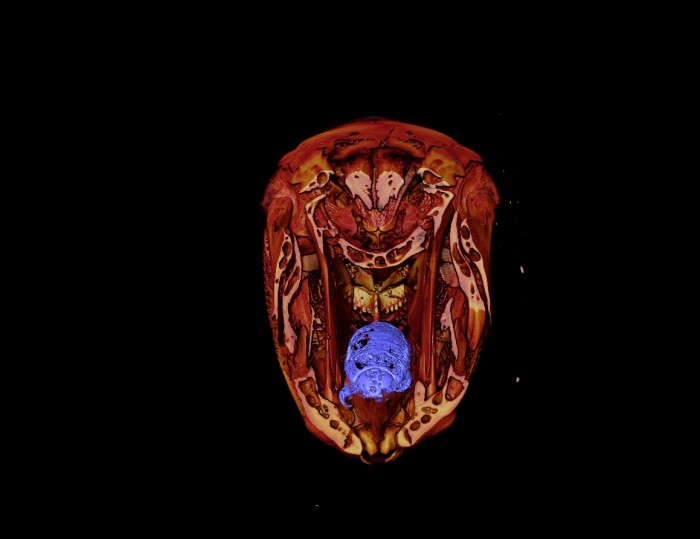

据外媒报道,鱼的生活并不轻松。它们必须躲避捕食者、渔网、污染以及现在想要吃掉它们舌头的吸血甲壳类动物。舌食虱子会侵入鱼的口腔,然后从鱼的舌头吸血并一直到舌头完全消失。最终,寄生虫取代了舌头本身。 莱斯大学生物学家Kory Evans在对鱼骨架进行X射线数字化时发现了这种令人毛骨悚然的咬舌者。

这种特殊的寄生虫是在新西兰发现的一条濑鱼身上发现的,当时Evnas正在对珊瑚鱼骨骼形态的3D X射线数据库进行研究。

Evans周三告诉Live Science:“它的嘴里好像有某种昆虫。然后我想,等一下,这条鱼是食草动物,它吃海藻。所以我拿出最初的扫描图,你瞧,它是一只吃舌头的虱子。”